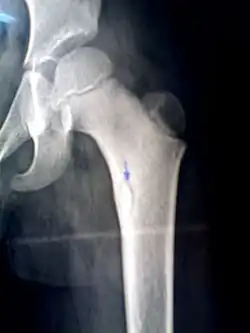

Секве́стр — участок омертвевшей ткани, свободно располагающейся среди живых тканей. Наиболее часто секвестр представляет собой некротизированный фрагмент кости при остеомиелите. Секвестрироваться может также ткань лёгкого, сухожилия, мышцы. Оставаясь в организме, секвестр постоянно поддерживает гнойное воспаление. Он может выделиться наружу самостоятельно с током гноя; в других случаях его удаляют хирургическим путём (секвестрэктомия).[1]